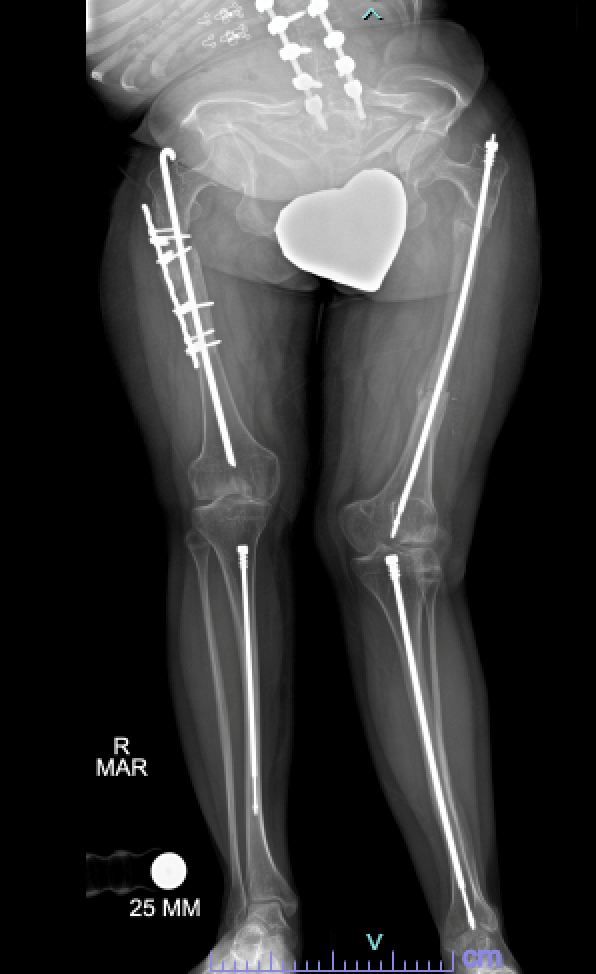

X-ray showing intramedullary rods in the legs of a patient with osteogenesis imperfecta

Intramedullary rods that lengthen with growth can be used to stabilize fractures, correct deformity, and reduce further fractures.

Rodding. Metal rods may be inserted in the long bones of the arms and legs to help reinforce the bone, and subsequently lessen the number of fractures. Some rods are a fixed length and must be replaced as a child grows. Other rods are designed like telescopes, and they expand as a child's bones grow. There are, however, other complications that may occur with telescoping rods. Do not hesitate to ask your orthopaedic surgeon about both rodding options.